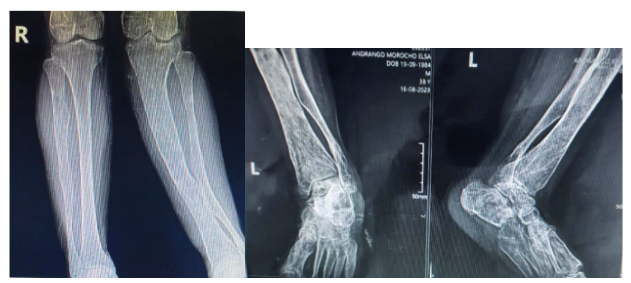

Figure 5. 5a AP radiograph of bilateral legs, 5b Anteroposterior and lateral radiograph of left ankle: tibia and fibula with increased bone density, bone with irregular and thin cortices, valgus deformity of tibia and fibula are observed.